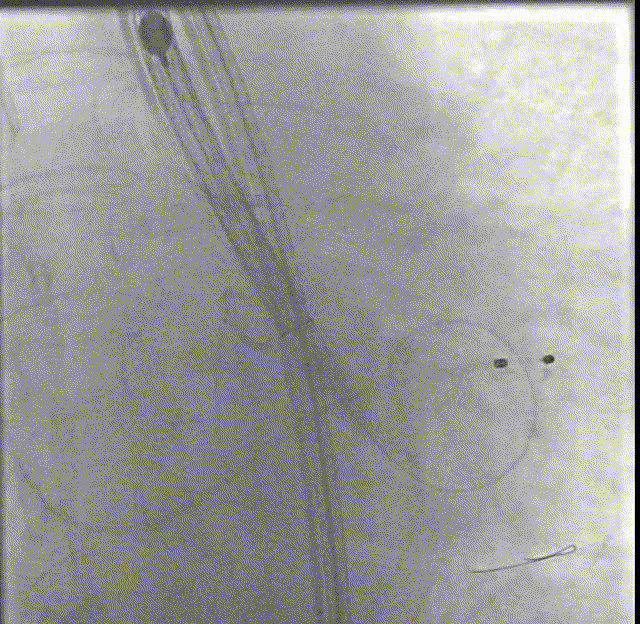

主动脉根部造影

18mm球囊预扩